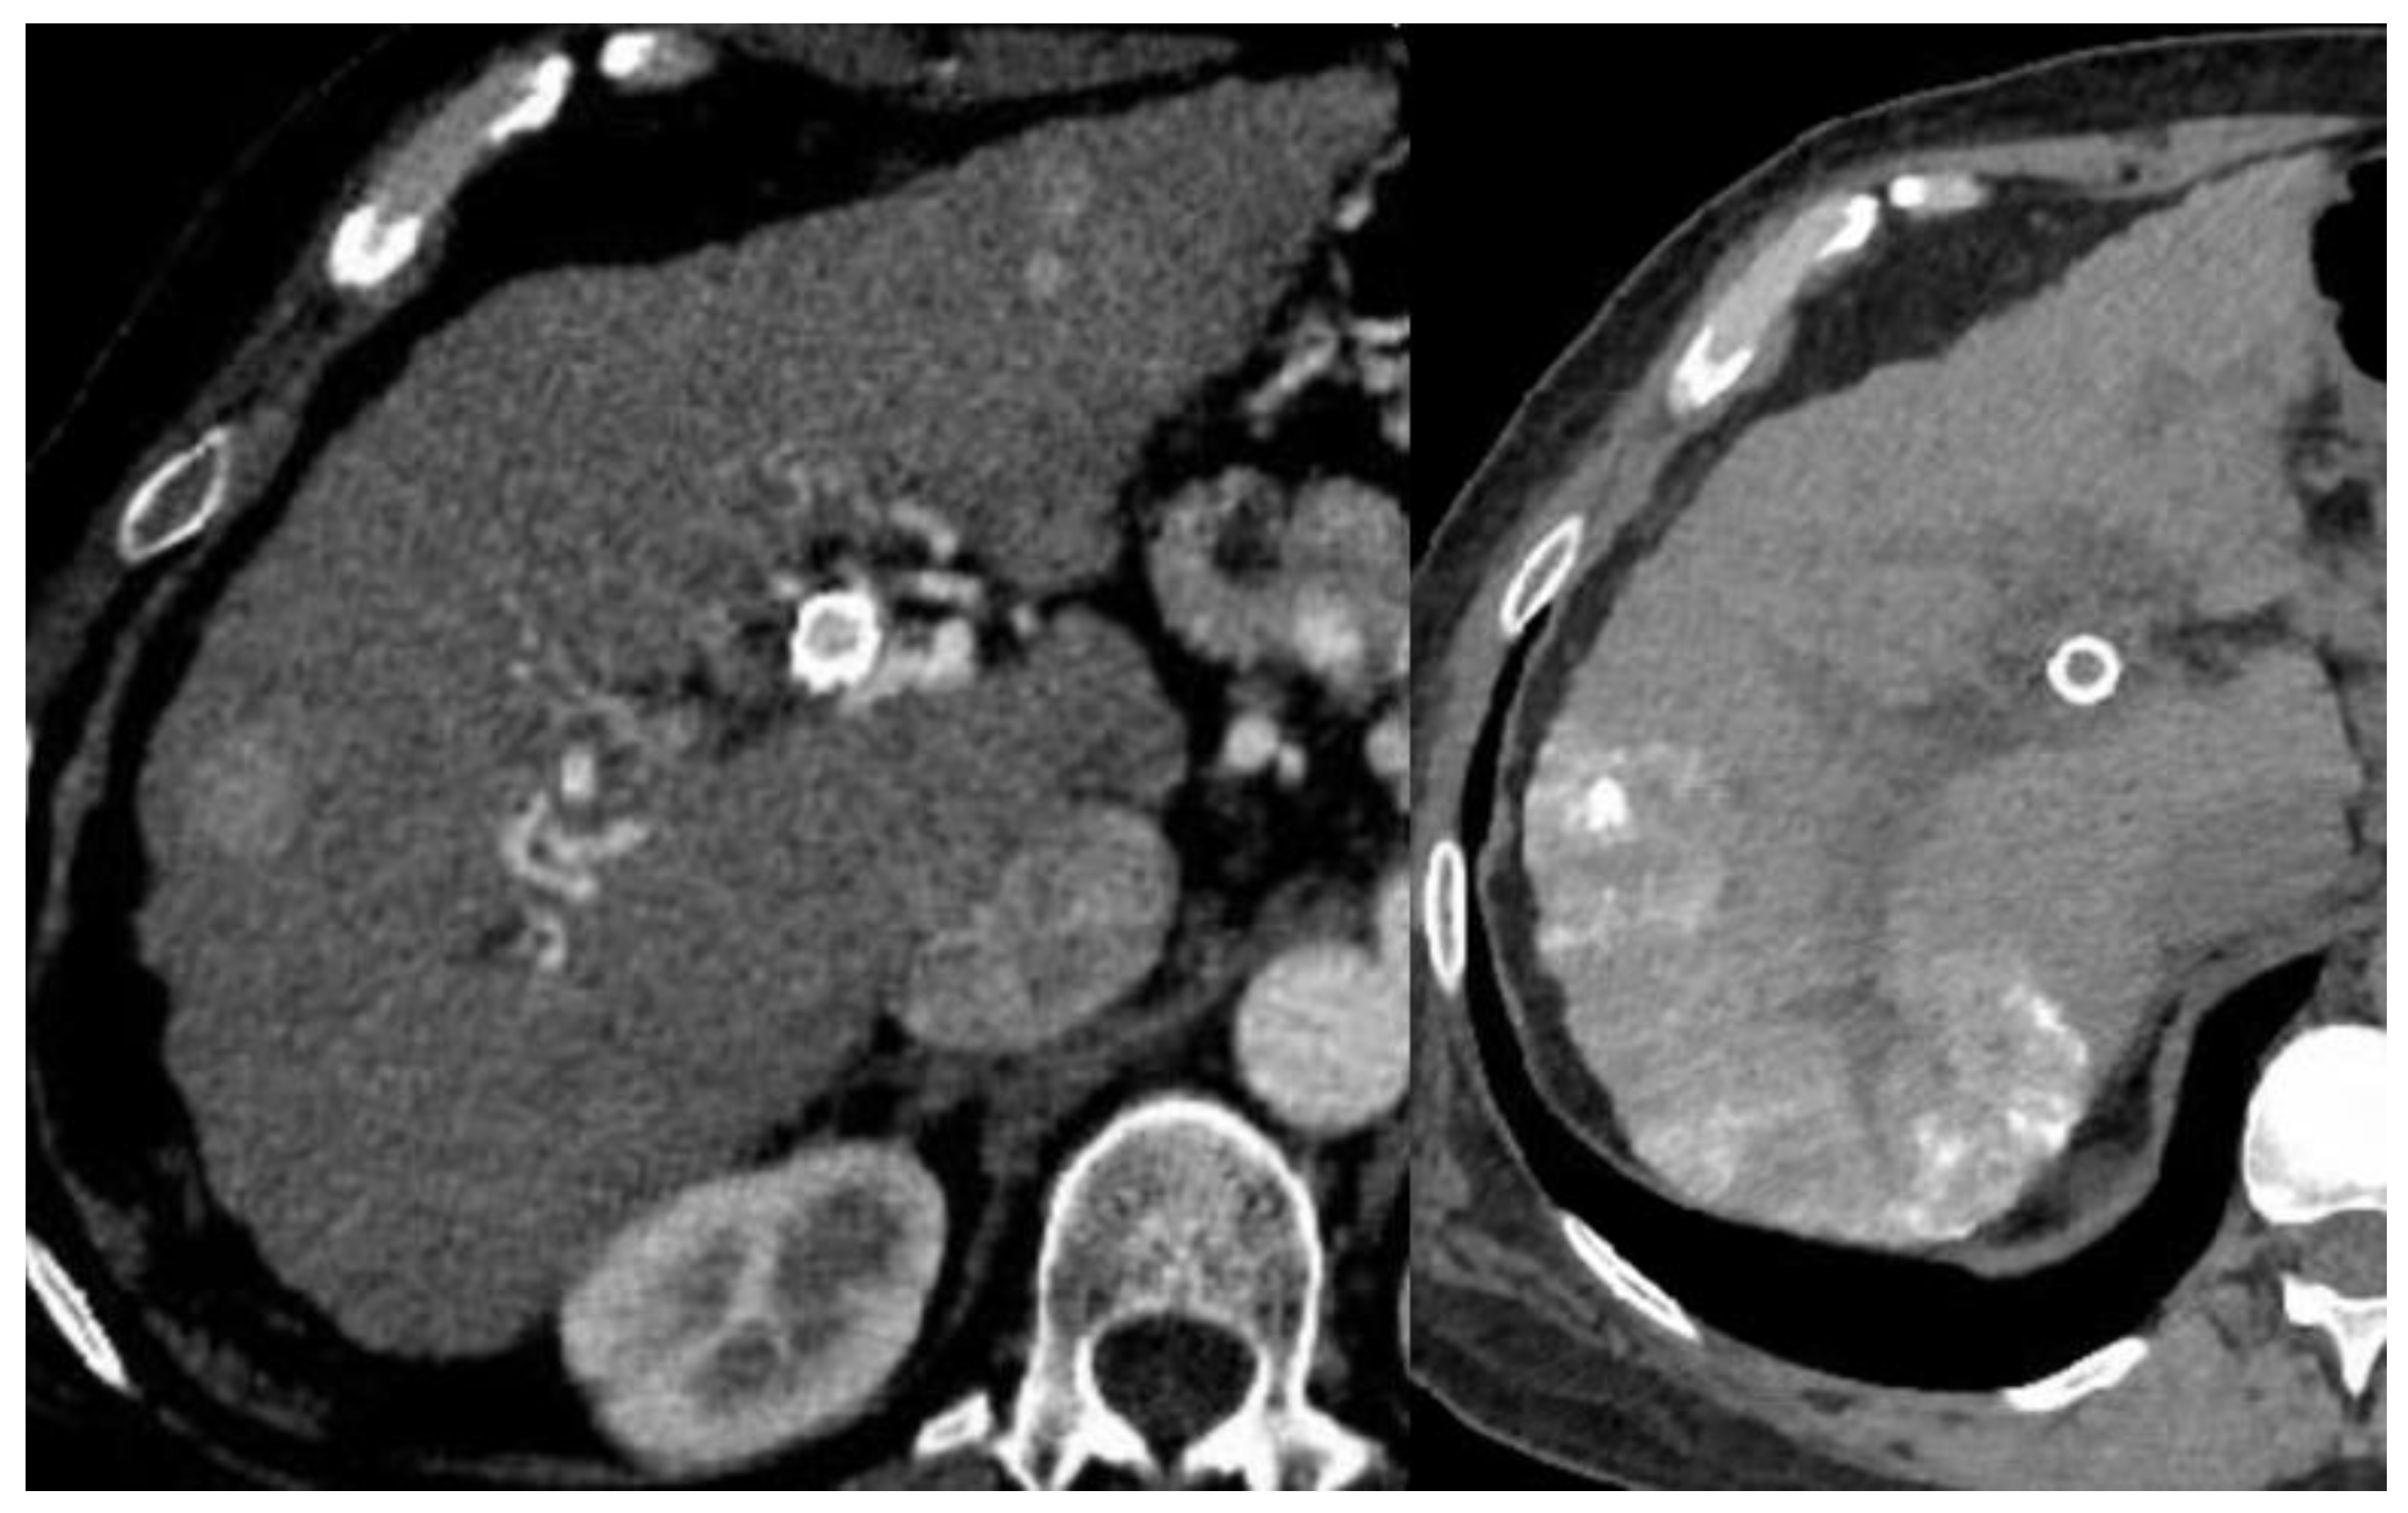

Figure 1.

Hepatocellular carcinoma pre- and post-TACE.

The image of a contrast-enhanced CT on the left shows a cirrhotic liver with arterial phase hyperenhancing segment 7 mass, corresponding to a known HCC. A non-contrast CT image on the right is post-TACE showing residual lipiodol in the right hepatic lobe.